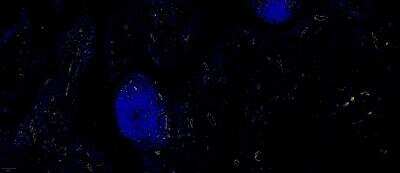

Immunocytochemistry/ Immunofluorescence

1-2 ug/ml